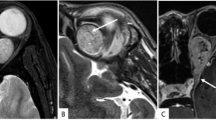

We report an 80-year-old male who presented with upper back pain for 3 months. Magnetic resonance imaging (MRI) showed a cystic lesion at the level of T6–T7 with peripheral contrast enhancement. The lesion was removed in total surgically with complete resolution of the patient’s symptoms.

The diagnosis of cystic schwannomas is often delayed due to the paucity of symptoms and the lack of meticulous investigation. The presence of rim enhancement on contrast-enhanced MRI may be the only clue for the diagnosis. It is important to consider cystic schwannomas in the differential diagnosis of cystic spinal lesions since the best surgical outcome is strongly related to earlier diagnosis and total resection of the lesion.